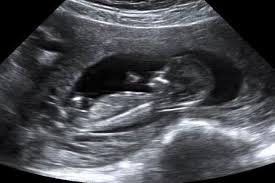

Y ahí estaba nadando pececito. El bienestar fetal de este bebé de 11 semanas de gestación parece evidente a juzgar por su movimiento de brazos y piernas. Semana 11 de Embarazo Ecografia.

A partir de la semana 11 cuando el feto mide entre 45 y 84 milímetros ya se realiza la ecografía de cribado de alteraciones cromosómicas y de alteraciones anatómicas mayores. Con apenas 12 semanas de embarazo este bebé ya cuenta con todas las estructuras corporales básicas que podrán verse en el momento del nacimientoEs un ser humano completo que podemos contemplar en ecografía 4DLo que le falta es tiempo de maduración para que todos sus órganos logren completar su desarrollo y la proporcionalidad entre la cabeza y las. En la semana 11 de gestación el feto mide alrededor de 4 cm desde la cabeza al coxis.

La cabeza representa la mitad de su longitud como se aprecia en esta silueta de perfil de una ecografía en 2D. Tu cuerpo en la semana 11 de embarazo gemelar. Te explicamos cómo evoluciona tu cuerpo a las 11 semanas de embarazo y cómo va creciendo tu bebé.